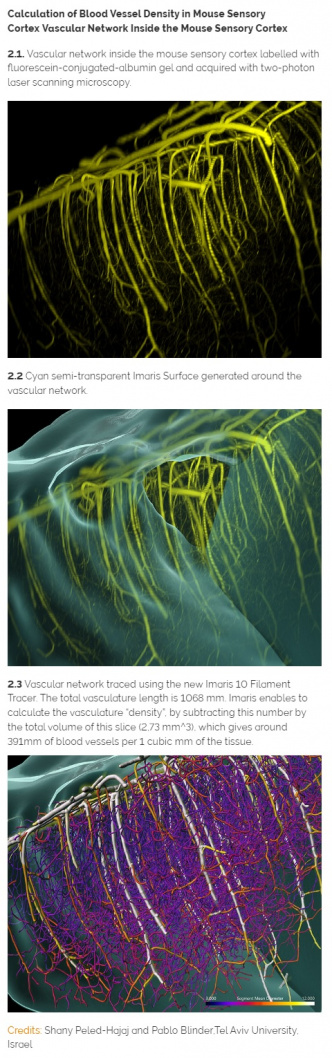

- Výzkum cév

Vědci, kteří se zajímají o sledování krevních cév, získají s verzí Imaris 10.0 nový algoritmus Loop pro efektivní detekci hustých cévních sítí v mozku nebo jiných orgánech. Charakteristickým rysem cévní sítě je velký rozdíl v průměru mezi hlavními hustými cévami a malými kapilárami. Z toho důvodu byla v programu Imaris 10.0 Filament Tracer zavedena nová funkce multi-scale seed point pro přesnou detekci a měření. Z modelu krevních cév mohou výzkumníci odvodit taková měření, jako je délka segmentu, celková délka krevní cévy, průměr, střední intenzita segmentu a orientace segmentů.

Vědci, kteří se zajímají o sledování krevních cév, získají s verzí Imaris 10.0 nový algoritmus Loop pro efektivní detekci hustých cévních sítí v mozku nebo jiných orgánech. Charakteristickým rysem cévní sítě je velký rozdíl v průměru mezi hlavními hustými cévami a malými kapilárami. Z toho důvodu byla v programu Imaris 10.0 Filament Tracer zavedena nová funkce multi-scale seed point pro přesnou detekci a měření. Z modelu krevních cév mohou výzkumníci odvodit taková měření, jako je délka segmentu, celková délka krevní cévy, průměr, střední intenzita segmentu a orientace segmentů.